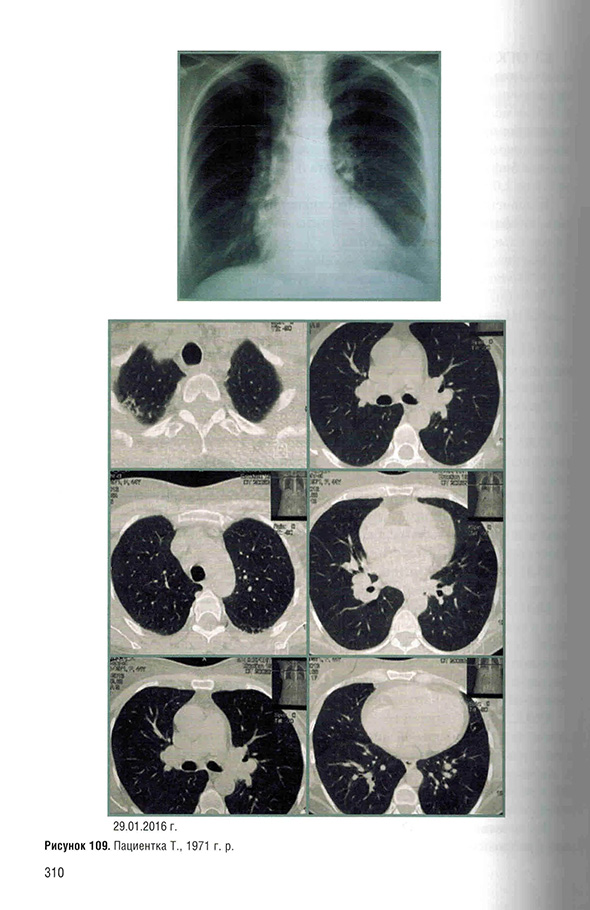

Примеры страниц из книги "Саркоидоз. Роль ренгенолога в мультидисциплинарном консилиуме" - Сперанская А. А.